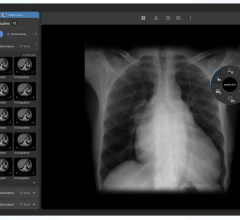

November 2, 2012 — ClearCanvas Inc. announced the commercial release of ClearCanvas radiology information systems/picture archive and communications systems (RIS/PACS) Team Edition, an end-to-end radiology workflow management solution.

The system is U.S Food and Drug Administration (FDA) cleared and CE marked and provides fully integrated radiology workflow and data management solution.

The RIS/PACS is built on the popular ClearCanvas software platform, currently in use by over 25,000 users and partners. The easy to use workflow solution has been designed to enable a practice to efficiently serve patients from the time they walk in the door to the time they receive their results.

The Team Edition includes key features such as drag and drop scheduling, customizable work lists, roaming user profiles, hanging protocols and digital report dictation. With web-based image viewing and the Referring Physician's Portal, it has also been designed for efficient and easy access to both patient images and associated reports.